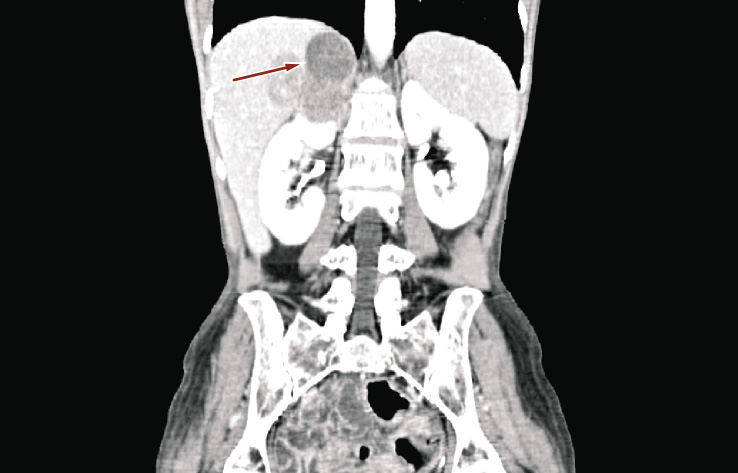

A 55-year-old woman was admitted to our Urology Unit on January 2014 to undergo a biopsy of right adrenal mass. Clinically, the patient suffered from continuous pain in the right lumbar region, a significant weight loss in the past two months (about 15 kg), and severe asthenia. Before hospitalization, ultrasonography showed a nonspecific mass located around the upper pole of the right kidney and abdominal computed tomography revealed a right adrenal neoplasm measuring 45 × 29 mm in diameter and bulging out toward the liver (Figures 1 and 2).

Figure 1. Ultrasonography showing right adrenal mass (red arrow) infiltrating the upper pole of kidney and liver (one month before hospital admission)